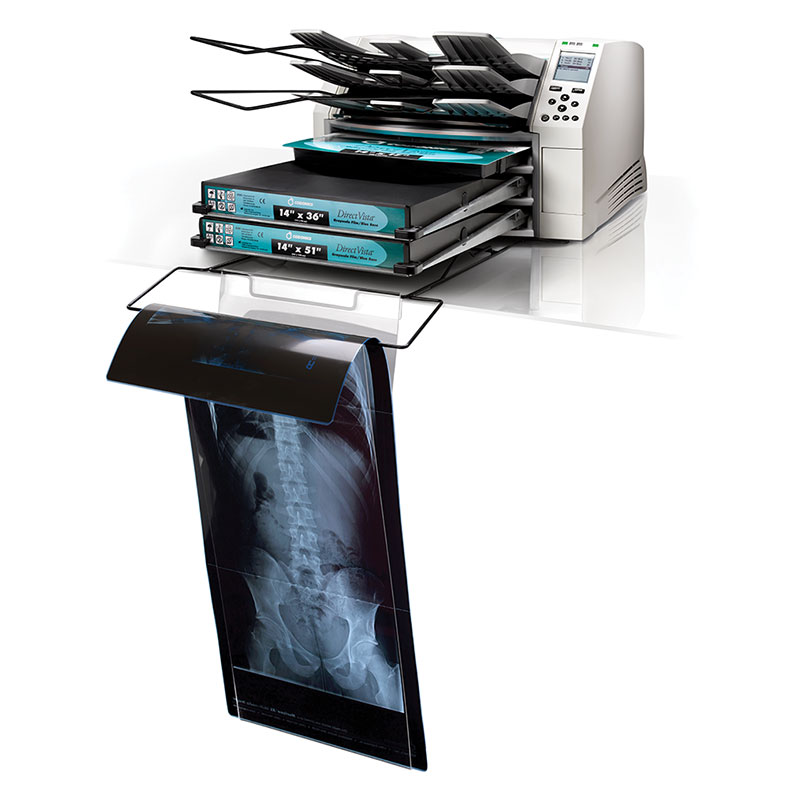

Horizon is three imagers in one – a dry film imager, color imager, and grayscale paper imager. Switching between film, color and paper requires no operator intervention. The all-in-one imager is an enormous breakthrough in performance, cost and quality for healthcare facilities.

The Horizon’s ultra-compact footprint easily allows it to be placed on a desk, counter, or in mobile applications. Requiring less than two feet (60.96 cm) of desk space and weighing less than 30kg, Horizon delivers superior diagnostic quality images and unmatched versatility. Its multiple media features make Horizon the ideal choice for different modalities, or a multiple modality department. Models available for every need and budget.

Horizon Hard Cassette

The Codonics Horizon hard cassette, designed for Codonics DirectVista® film, is reusable and refillable to reduce waste. The cassette quickly adjusts to accommodate three film sizes, including 35×43 cm (14×17), 28×35 (11×14) or 20×25 cm (8×10) and holds up to 100 sheets. The cassette uses Horizon MediaID technology, an RFID-based media identification and security platform to ensure film quality and authenticity. Codonics Horizon is compatible with both hard cassettes and soft cassettes on line at the same time to provide simultaneous printing on all sizes of film and paper.